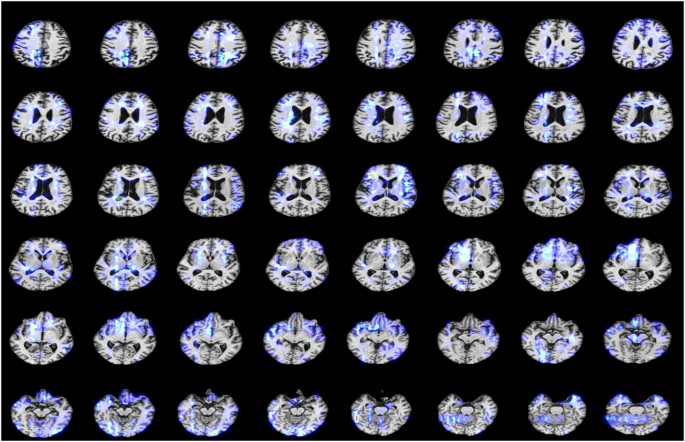

We consecutively annotated the complete MRI scans of several individuals, one of whom is shown in Fig. 6, and used FreeSurfer to segment brain structures. This allowed us to compare them with standard anatomical atlases and determine whether key regions were annotated.

-

In the upper-layer MRI of this patient, our annotations focus on the medial temporal lobe structures and parts of the temporal cortex, which are commonly affected regions in AD pathology. Annotations also appear around the ventricles (dark areas), as ventricular enlargement is an indirect manifestation caused by brain tissue atrophy in AD patients11.

In the upper-middle-layer MRI, blue annotation regions cover the hippocampus and medial temporal lobe structures, and also involve the lateral ventricles (dark areas). Due to brain tissue atrophy, ventricular enlargement often occurs in AD patients. Upper-middle images begin to show the frontal and parietal regions, and annotations also cover these cortical areas. In mid-to-late-stage AD, frontal and parietal atrophy becomes more evident, affecting executive functions and spatial cognition12.

In the middle-layer MRI, yellow-highlighted regions are located in the medial temporal lobe near the brain’s midline, where the hippocampus lies. Extensive blue annotations are present in both temporal lobes, regions commonly affected in AD. Additionally, some blue regions near the top involve the parietal and frontal lobes but are less distributed 13.

In the lower-middle-layer MRI, yellow-highlighted regions remain in the medial temporal lobe, especially the hippocampus. Blue annotations are visible in both temporal lobes, covering parts of the inferior and middle temporal gyri. Annotations near the midline involve white matter regions around the ventricles, often associated with white matter lesions.

In the lower-layer MRI, annotations are concentrated in middle-lower areas (bilaterally symmetrical, near the ventricles), key regions commonly affected in AD patients. Annotations are also present in the temporal lobes on both sides, particularly the medial temporal lobe. Regions around the central ventricles and upper image areas (frontal lobe) are also annotated, which is commonly seen in AD patients 14.

The continuous annotation performance for a single AD (Alzheimer’s Disease) patient.

In summary, our annotations accurately covered key brain regions commonly affected in AD patients, including the medial temporal lobe, hippocampus, temporal cortex, and regions around the ventricles. These annotations closely align with AD pathological characteristics, such as brain tissue atrophy and ventricular enlargement. They not only correspond to standard anatomical atlases but also reliably reflect AD-related features, providing a robust foundation for subsequent pathological analysis and diagnosis. Our annotation results are highly consistent with those of Qiu et al.7.